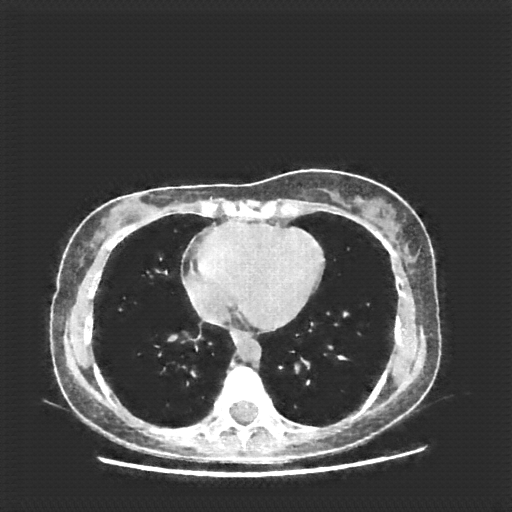

Original VENOUS CT scan

Mediastinum window (WL 40, WW 400 β†’ Low βˆ’160, High +240)

Actual HU range: [-160.0, 240.0]